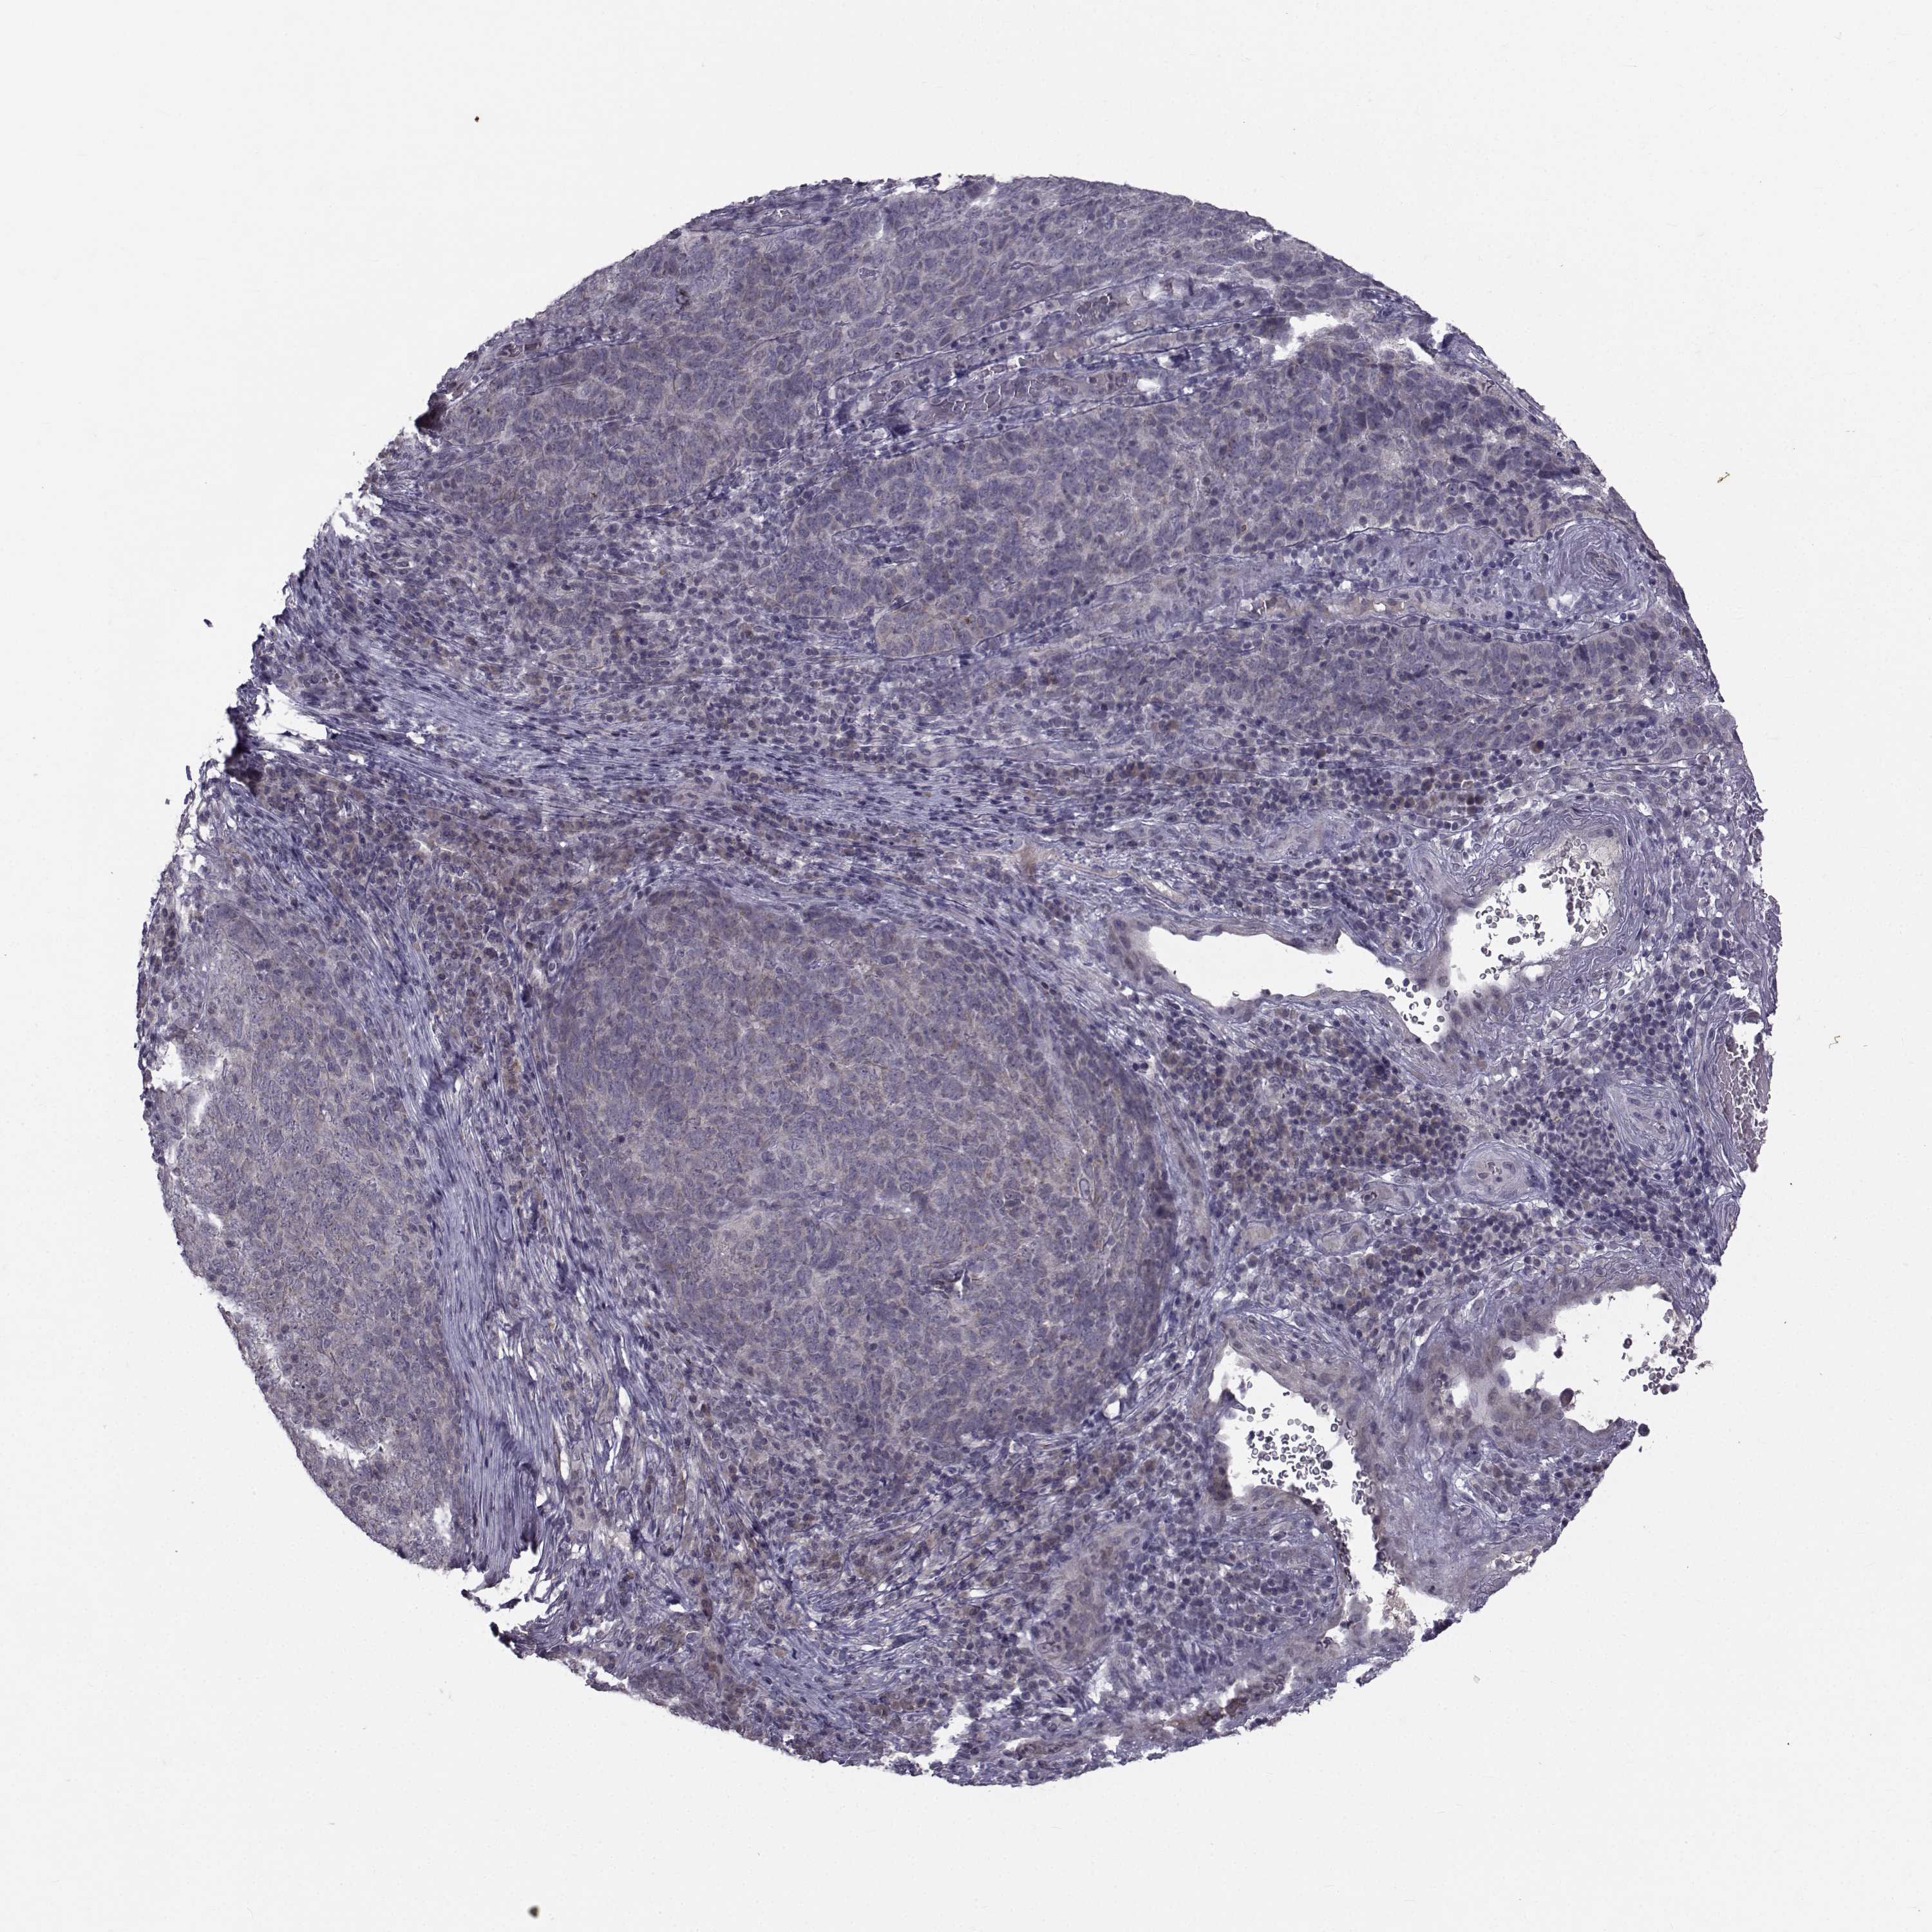

CANCER SKIN CANCER Show tissue menu

SKIN CANCER - Protein expressioni

A mouse-over function shows sample information and annotation data. Click on an image to view it in a full screen mode. Samples can be filtered based on level of antibody staining by selecting one or several of the following categories: high, medium, low and not detected. The assay and annotation is described here.

Each image is clickable and will lead to virtual microscopy that enables deeper exploration of all samples and also displays staining intensity scores, fraction scores and subcellular localization as well as patient and tissue information for each sample.

Antibody HPA044393

Squamous cell carcinoma, NOS

Basal cell carcinoma